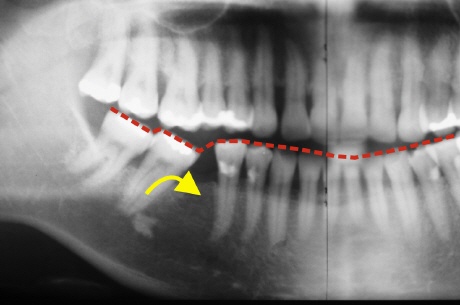

Das Bild oben zeigt, was es für Auswirkungen habe kann, wenn durch einen Zahnverlust eine unversorgte Lücke bestehen bleibt. Die stabilität der Zahnreihe ist gestört und die hinteren Seitenzähne kippen (gelber Pfeil) in die Lücke). Weil die Zähne nicht entsprechend Ihrer Achse nach vorn wandern, sondern kippen, verändert sich auch die gesamte Verzahnung (Okklusion) mit den oberen Zähnen. Dies führt nicht selten erst nach vielen Jahren zu beschwerden in der Kiefergelenksregion, da die Kiefergelenke mit den entsprechenden Bändern und Muskeln diesen veränderte System kompensieren müssen. Der entspandene Schaden durch die viele Jahre nicht versorgte Lücke ist nun viel aufwendiger und schwieriger zu versorgen, als die unmittelbar nach der Zeit des Zahnverlustes war.